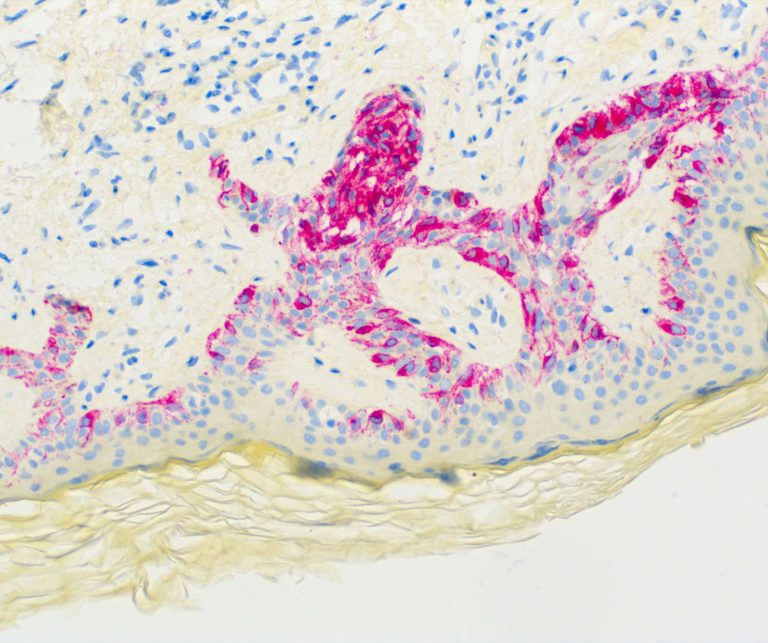

Vascular Pathology